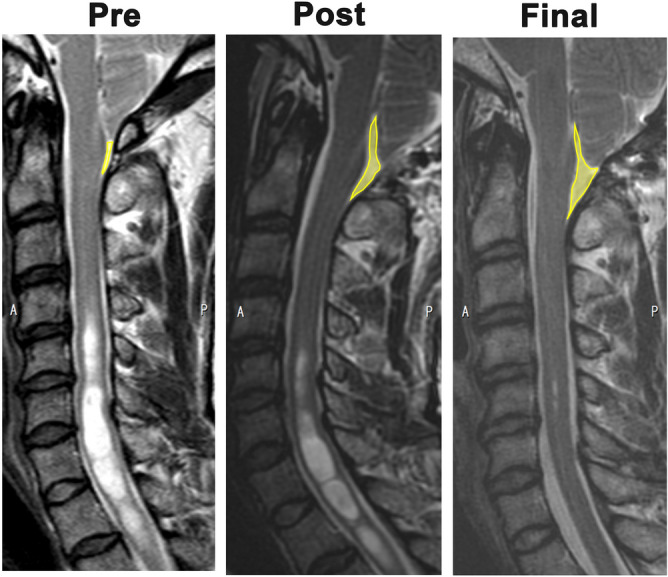

We measured the area of the pSAS between the cerebellar tonsils and C2 in the midline sagittal image on T2-weighted imaging (T2WI) before surgery, immediately after surgery, and at follow-up. The sagittal slice position and orientation were adjusted so that the slice plane was perpendicular to the cervical vertebral body in anterior–posterior axis and left–right axis. The mid-sagittal slice was selected from multiplanar (axial, coronal, sagittal) images. The pSAS area was obtained using manual delineation with the Image J software program15. Two examiners measured the pSAS area. We calculated the inter-rater reliability for the pSAS measurements. ICC2Ck was 0.995. pSAS was enlarged sequentially over time after FMD (Fig. 1). The ratios of the pSAS area immediately after surgery and at follow-up to the preoperative pSAS area were calculated. The percentage increase in pSAS area was calculated by dividing the difference between the pre- and postoperative values by the preoperative value. Syrinx resolution was defined as a decreased syrinx area on midline sagittal images of T2WI. The maximum syrinx/spinal cord length ratio and overall syrinx length were also measured to assess syrinx resolution after FMD. A 20% reduction in the syrinx/cord ratio or overall length at the last follow-up was defined as syrinx resolution.

Figure 1.

pSAS was defined as the area between the dura mater and spinal cord from the foramen magnum to C2 on a midline sagittal image on T2-weighted imaging. The yellow line represents the outline of the pSAS. Representative MRI image with syrinx improvement. Right, preoperative images; Middle, postoperative images; Left, images at final follow-up.